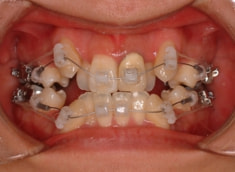

治療後(2年3ヶ月後)

歯根のパラレリング(平行性)が獲得されております。

下顎8番は、両側抜歯済みです。

顎位は良好な状態です。